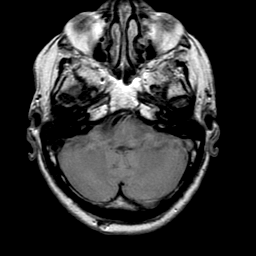

Meningioma, MR Study #1 -- Slice #3

[Home][Help][Clinical] Slice 3